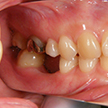

8. 施術前右側観

6番部の欠損です。両隣在歯は良い歯をしています。絶対削りたくありません。ましてやブリッジにするために、最後臼歯の咬頭関係を崩してまで削るのは、咬合を崩すことになります。単独インプラント適応です。22歳です。